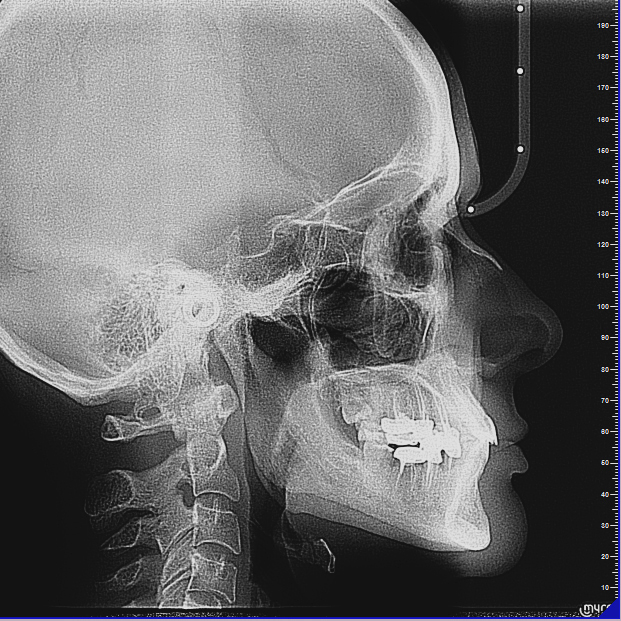

Современная диагностическая база

• Конусно-лучевая компьютерная томография